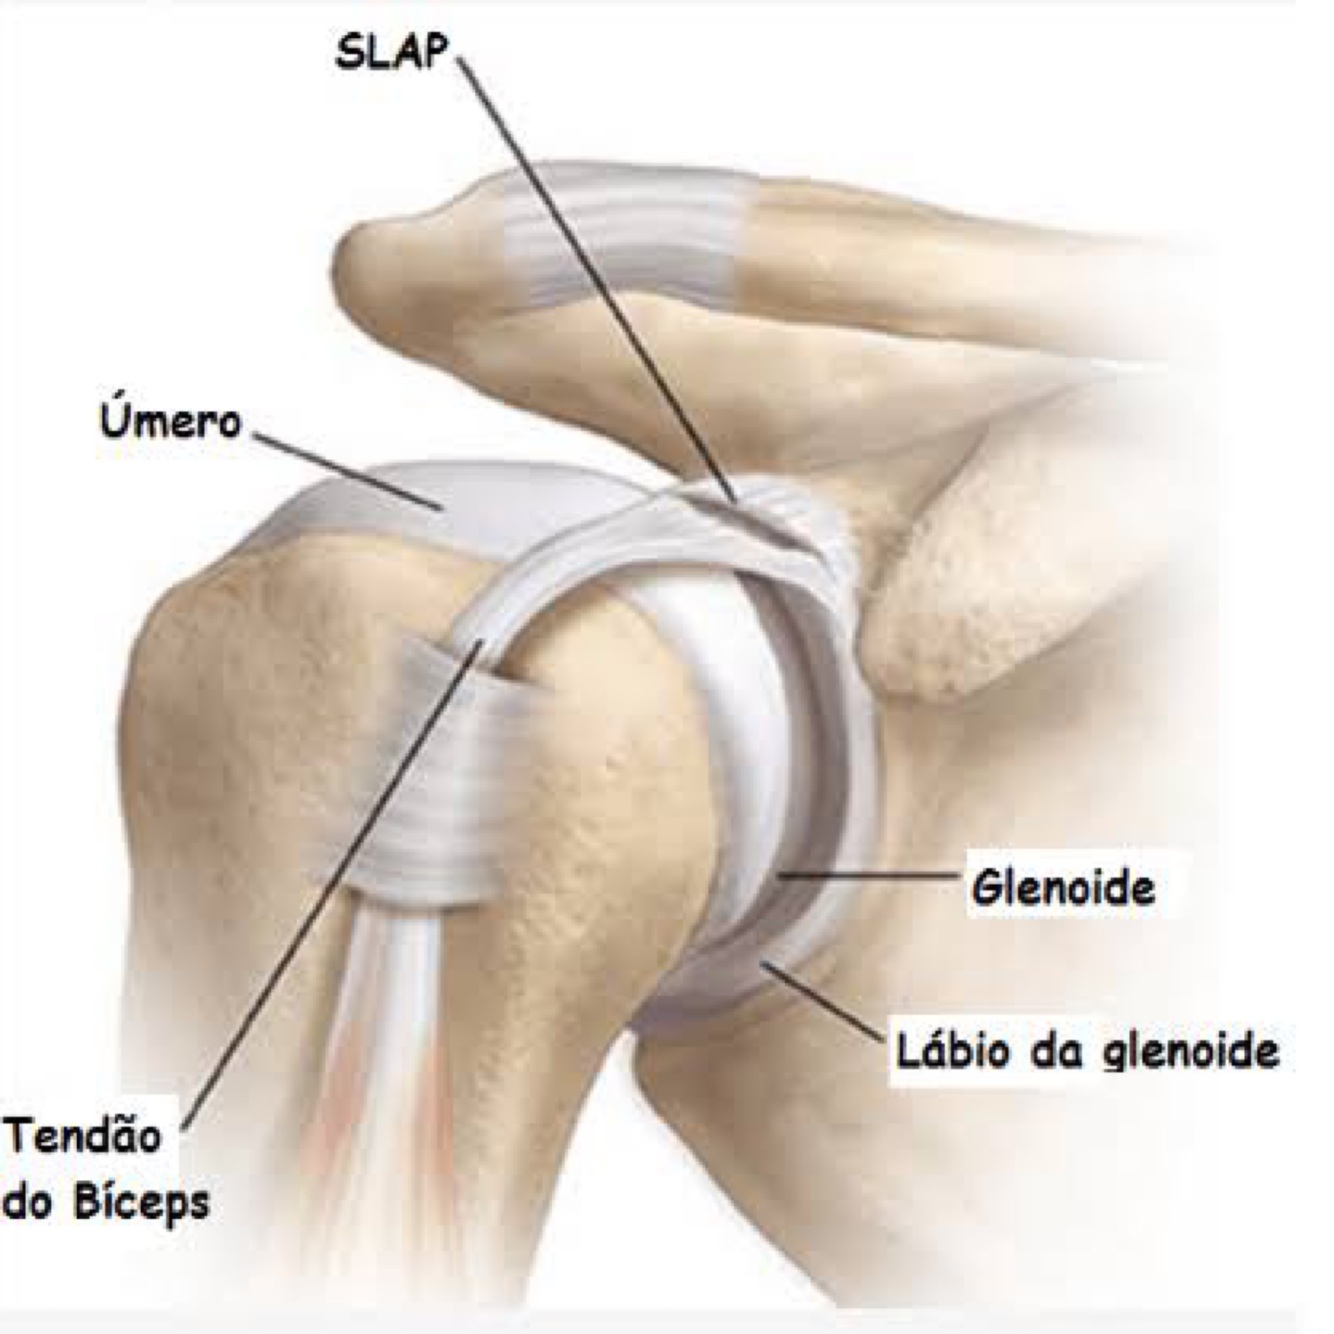

O que é lesão de bankart ?

Lesão anterior inferior do labrum

O que é lesão de Hill sachs?

Lesão póstero superior cabeça do úmero